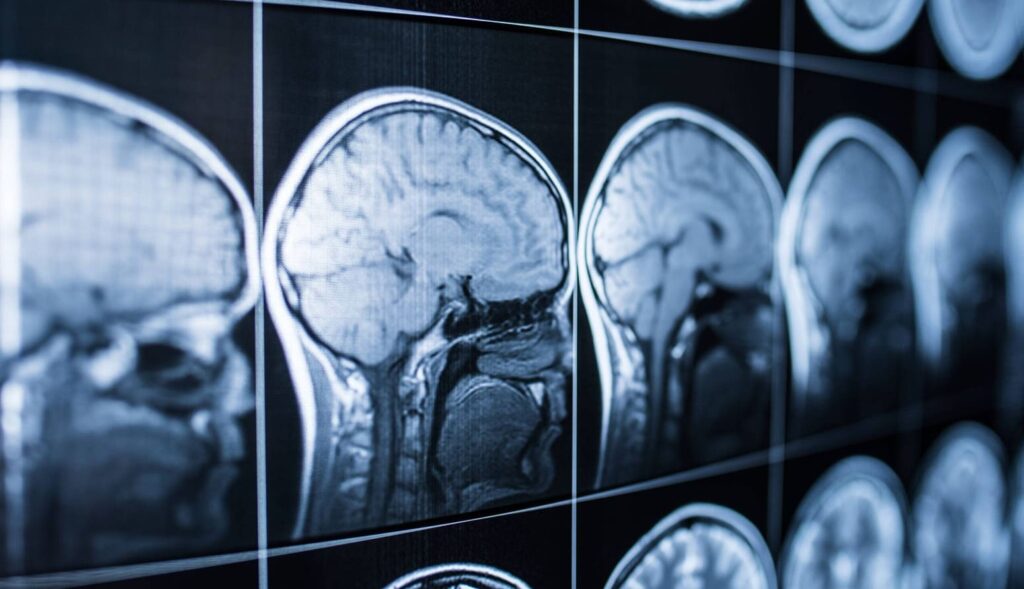

Para investigar este fenómeno, el equipo utilizó resonancia magnética funcional (fMRI) mientras los participantes realizaban una tarea en la que debían elegir entre honestidad y beneficio económico. También evaluaron cómo juzgaban el comportamiento de otros en la misma situación.

Las personas coherentes aplicaban criterios similares a sí mismas y a los demás, con patrones de activación comparables en la vmPFC. En cambio, quienes eran más indulgentes consigo mismos mostraban menor actividad y menor conexión de esta región con otras implicadas en la toma de decisiones.